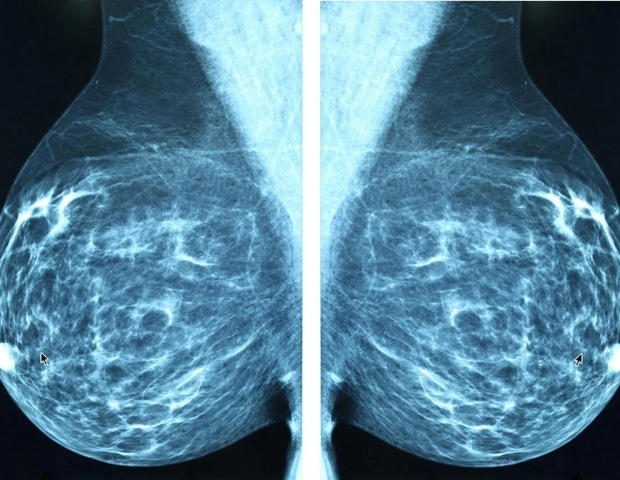

Αναγνώριση μεταστατικών κυττάρων μέσα σε πρωτογενείς όγκους μαστού

Η συγκεκριμένη μελέτη, που δημοσιεύθηκε στο περιοδικό Nature Communications, συνδυάζει την ανάλυση ενός μοντέλου ποντικού με καρκίνο του μαστού και δεδομένα από ασθενείς. Τα αποτελέσματα έδειξαν ότι, στην επεμβατική εμπρόσθια ζώνη του όγκου, υπάρχει ένα συγκεκριμένο πληθυσμό κυττάρων που είναι ικανά να εισβάλλουν και να είτε να πολλαπλασιάζονται είτε να εισέρχονται σε κατάσταση ύπνου. Αυτή η ισορροπία καθορίζει το αν τα κύτταρα που διαφεύγουν από τον όγκο μπορούν να ξεκινήσουν νέους όγκους σε απομακρυσμένα όργανα.